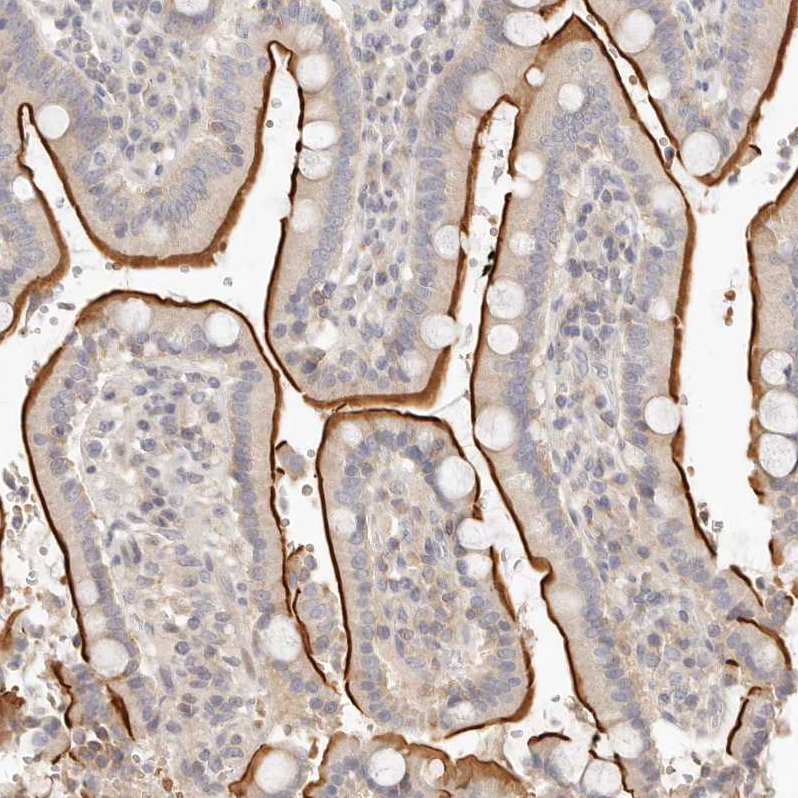

Immunohistochemical staining of human cervix, uterine shows moderate membranous positivity in squamous epithelial cells.